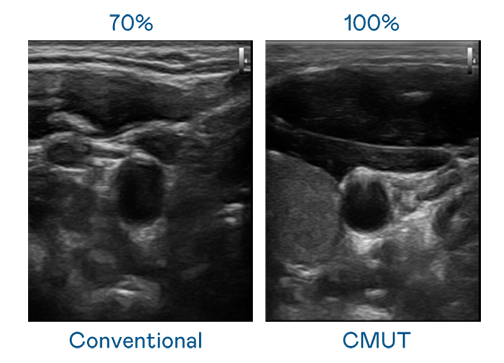

申博太陽城運用 TFT 陣列 (Array) 制程延伸尖端感測技術 ,開發(fā)出多種感測元件的產(chǎn)品。高解析度、品質穩(wěn)定且可量產(chǎn)的 CMUT 元件 ,可制作高解析度超音波探頭 、貼片型探頭 ,對病患實施精準檢測與長時間生理監(jiān)測 。為滿足 X光設備輕量化、可移動 ,甚至需針對待測物進行外觀客制化的新需求 ,申博太陽城結合非晶矽 (a-Si) 制程與新的封裝技術 ,實現(xiàn)可撓曲、具優(yōu)異 TFT 遷移率 (mobility) 的柔性 X光感測器。目前也已提供完整玻璃和曲面型 X光感測器檢測解決方案 。